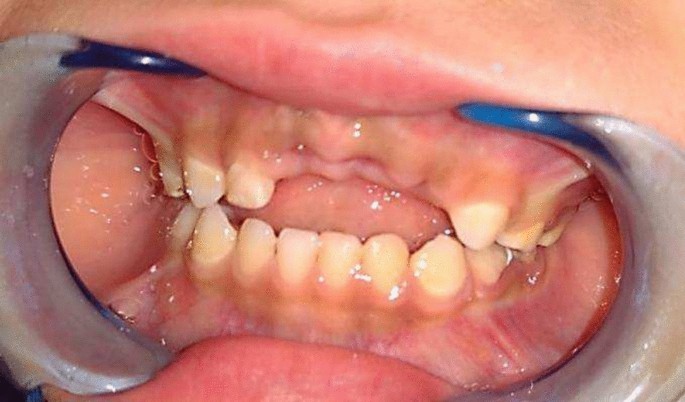

Group II (control group): Twenty preschool children used a modified Nance appliance in their anterior extraction site. (Fig4, 5)

Premature loss of upper ant teeth.

Rehabilitation of extraction site with modified Nance appliance.